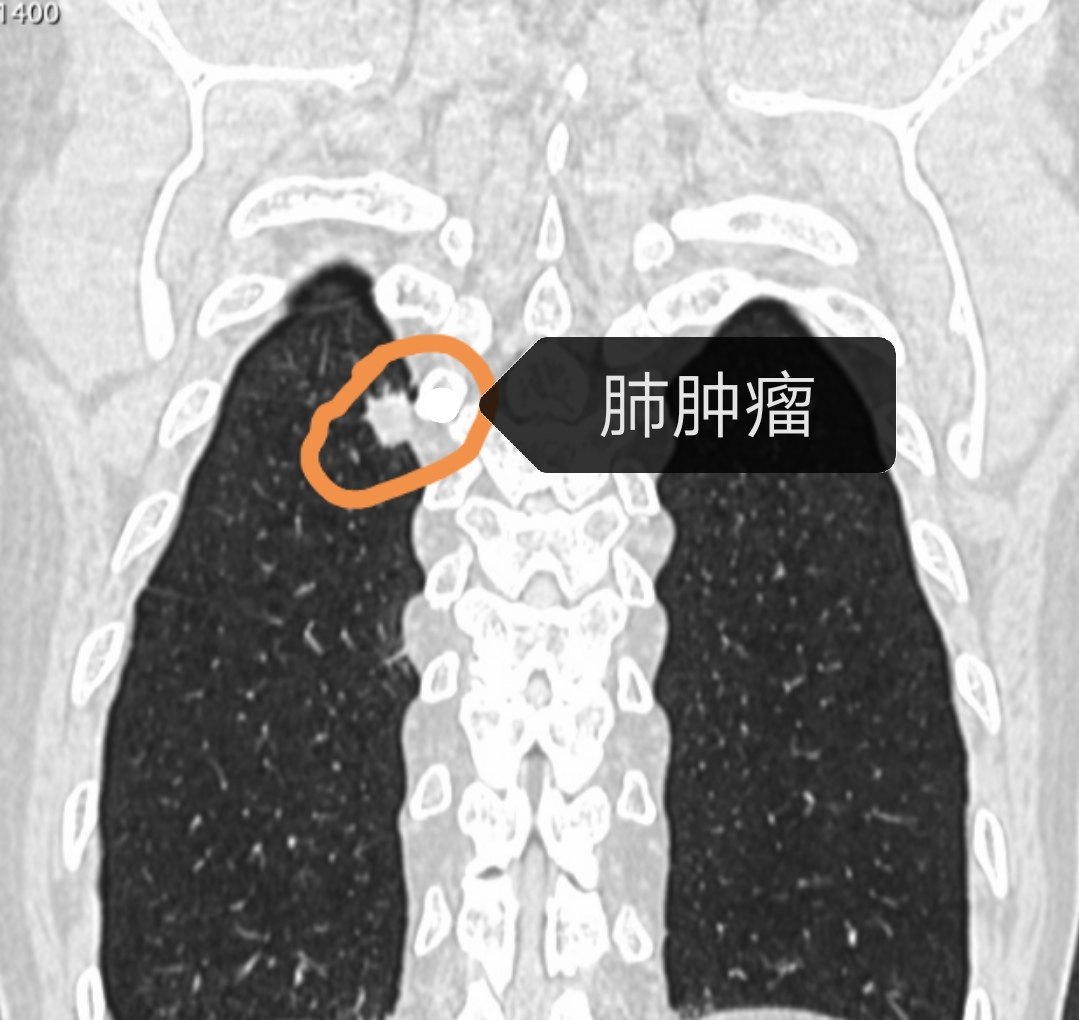

肺部肿瘤胸片

肺部肿瘤胸片,肺部肿瘤图片

图1胸片示右肺上叶病变(圆圈),组织活检为腺癌.